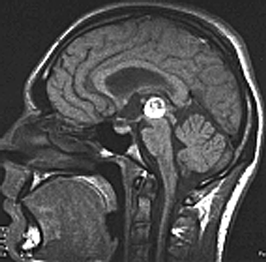

При МРТ пинеоцитома выглядит как хорошо отграниченное образование, иногда с кистозным компонентом, не инфильтрирующее соседние структуры (рис. 3).

Рисунок 3. Пинеоцитома шишковидной железы (МРТ, Т1-взвешенное изображение)